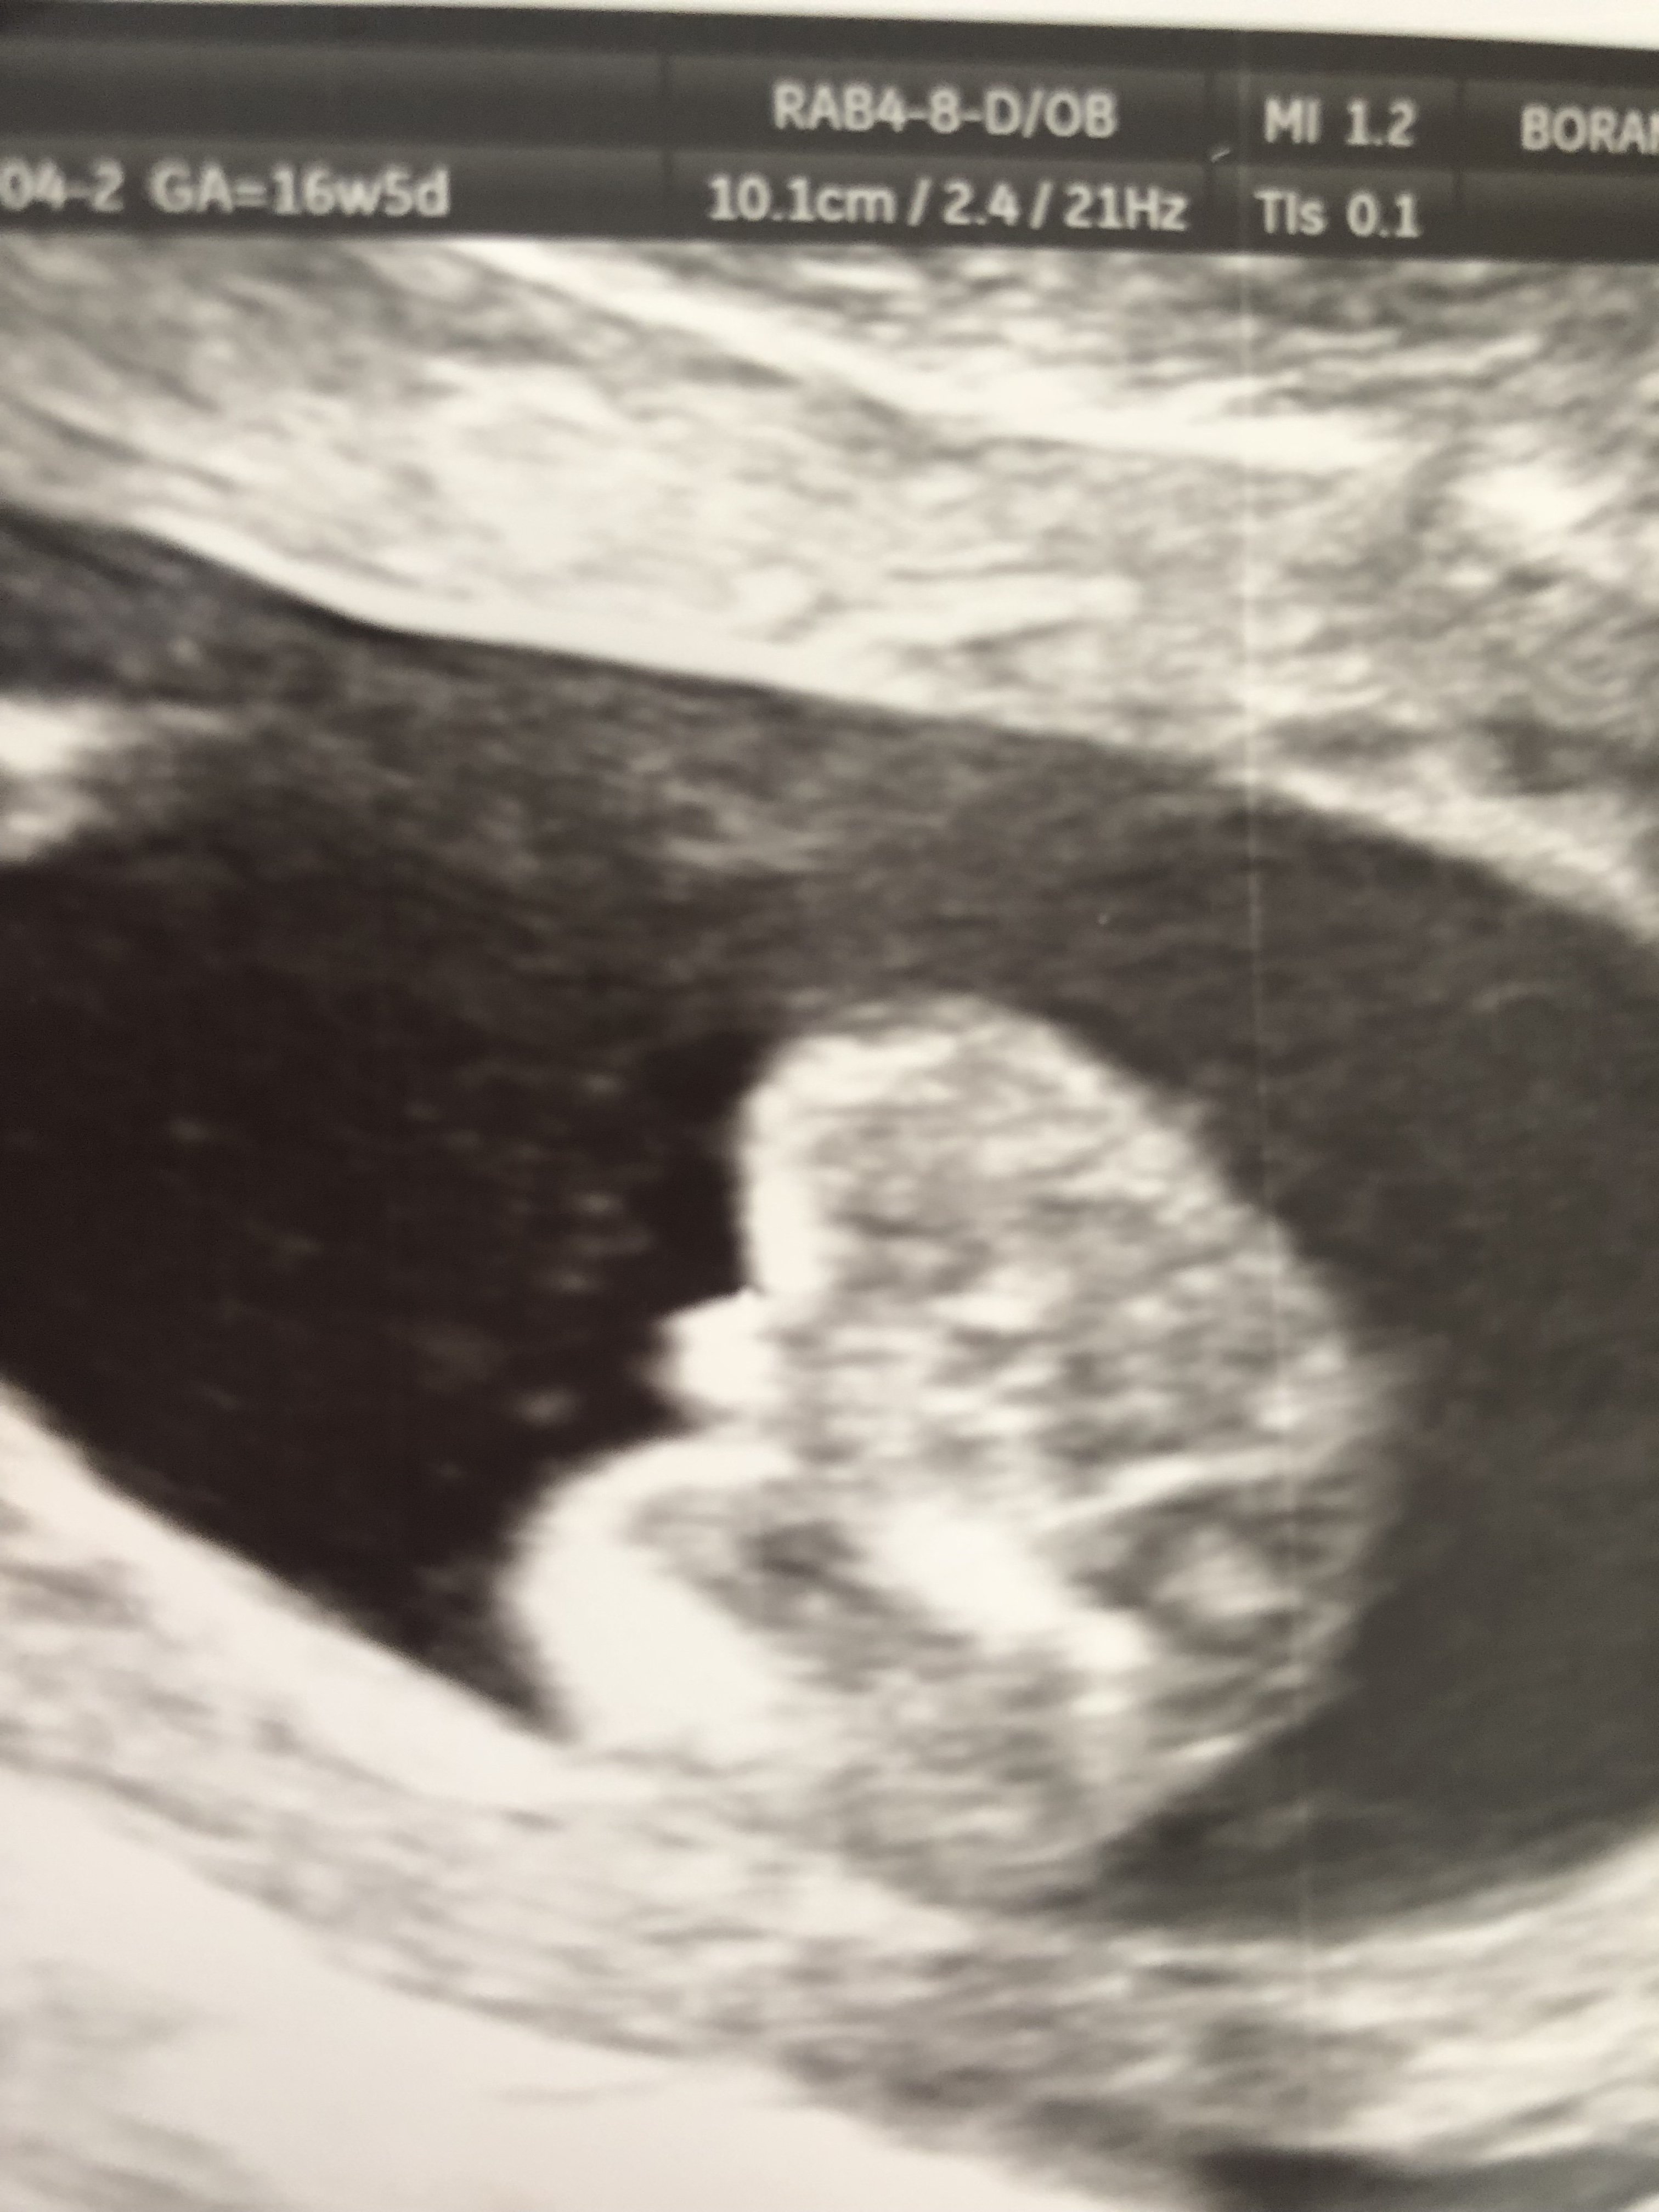

Cześć dziewczyny, dzisiaj byłam u ginekologa który z 90% pewnością stwierdził ze nosze pod sercem synka, później dzidziuś przeskakiwał i się wyginał i ciężko było coś uchwycić, dziwnie mam wrażenie ze obydwa zdjęcia które otrzymałam jednak się różnią.

Co myślicie, chłopak ?

• 9700FCD7-8538-4CB3-9F7F-976649A8D586.jpeg

9700FCD7-8538-4CB3-9F7F-976649A8D586.jpeg

840,4 KB · Wyświetleń: 473